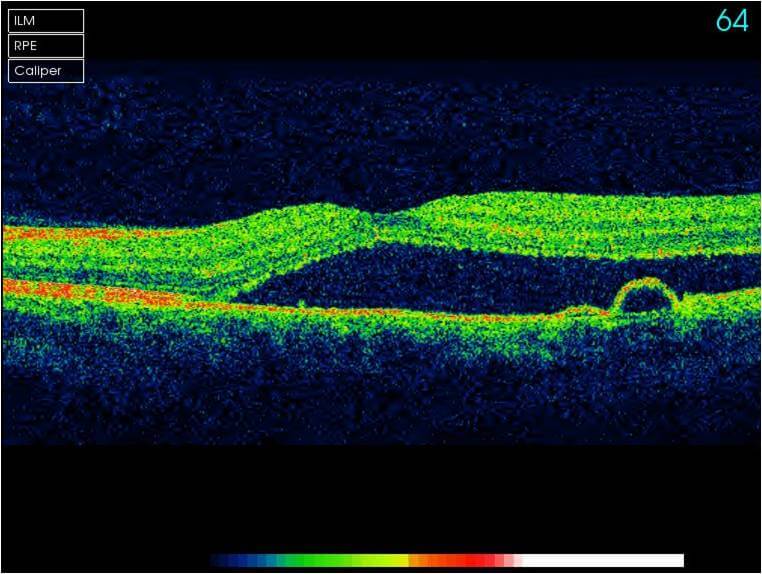

Optical Coherence Tomography (OCT) is an advanced eye scan, similar to ultrasound. The OCT uses light rather than sound waves to illustrate the different layers that make up the back of the eye. Within 2 seconds, the OCT takes over 30,000 individual scans of the back of the eye and this is used to produce a 3D image of the retina and optic nerve. The scan gives an accurate cross-sectional map through the retina and allows examination of the back of the eye in incredibly fine detail.

An OCT scan will allow us to detect and monitor any changes to your eye health much earlier than other methods of screening your eyes. The early detection of eye conditions such as glaucoma allows treatment to be offered long before any symptoms are noted.

The scan shows us beneath the surface of your retina, so we can see and better understand the very fine changes which can be indications of something unhealthy or abnormal.

With all your scans stored with your records, we are able to easily compare the OCT images from test to test and can quickly pinpoint any changes to the health of your eyes.